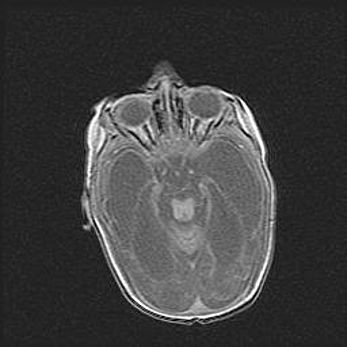

Церебральная ишемия II.

Возраст: 5 дней

Вес: 3400 г

Пол: женский

Окружность головы: 35 см

Срок гестации: 39 недель

Церебральная ишемия – это заболевание, характеризующееся недостаточностью (гипоксией) либо полным прекращением (аноксией) снабжения мозга кислородом по причине закупорки одного или нескольких сосудов. Это приводит к  что метаболическим расстройствам различной степени тяжести в тканях головного мозга, развитию коагуляционных некрозов и гибели нейронов.